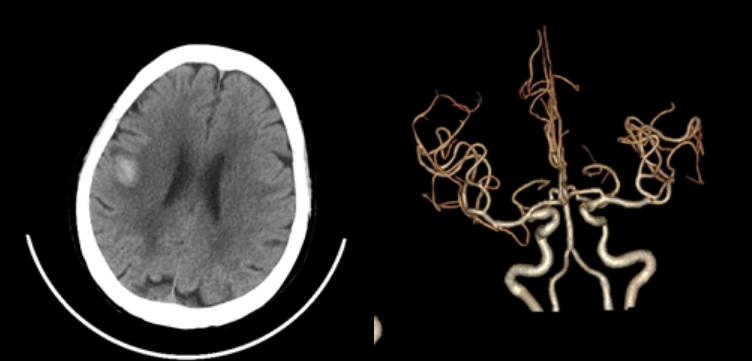

十八、脑出血合并开窗畸形

病例34:左侧基底节区脑出血合并右侧大脑前动脉A2段开窗畸形